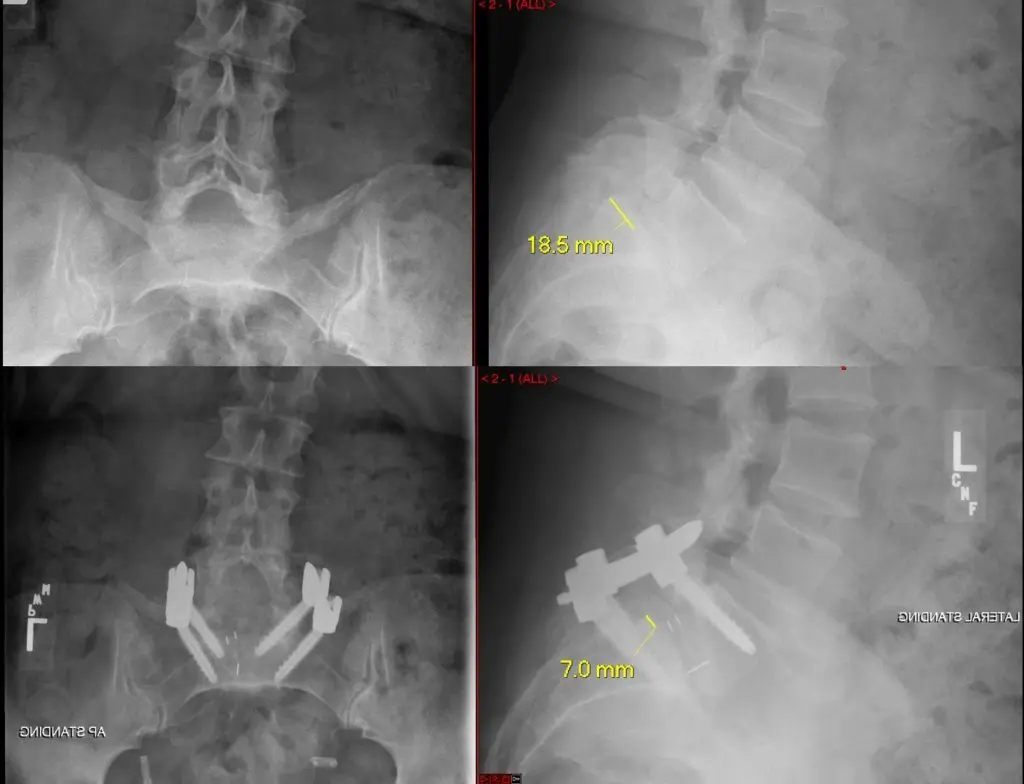

Figure above shows a patient with spondylolytic spondylolisthesis who had traditional surgery 15 years ago. This shows the screw placement in a divergent position that has unfavorable biomechanical property compared with a convergent position. An accurate screw placement is a prerequisite to achieve a successful reduction of the slip.

These scans above were taken before (upper panel) and after (bottom panel) the surgery, and show the placement of the screws with a larger convergence to ensure stability.